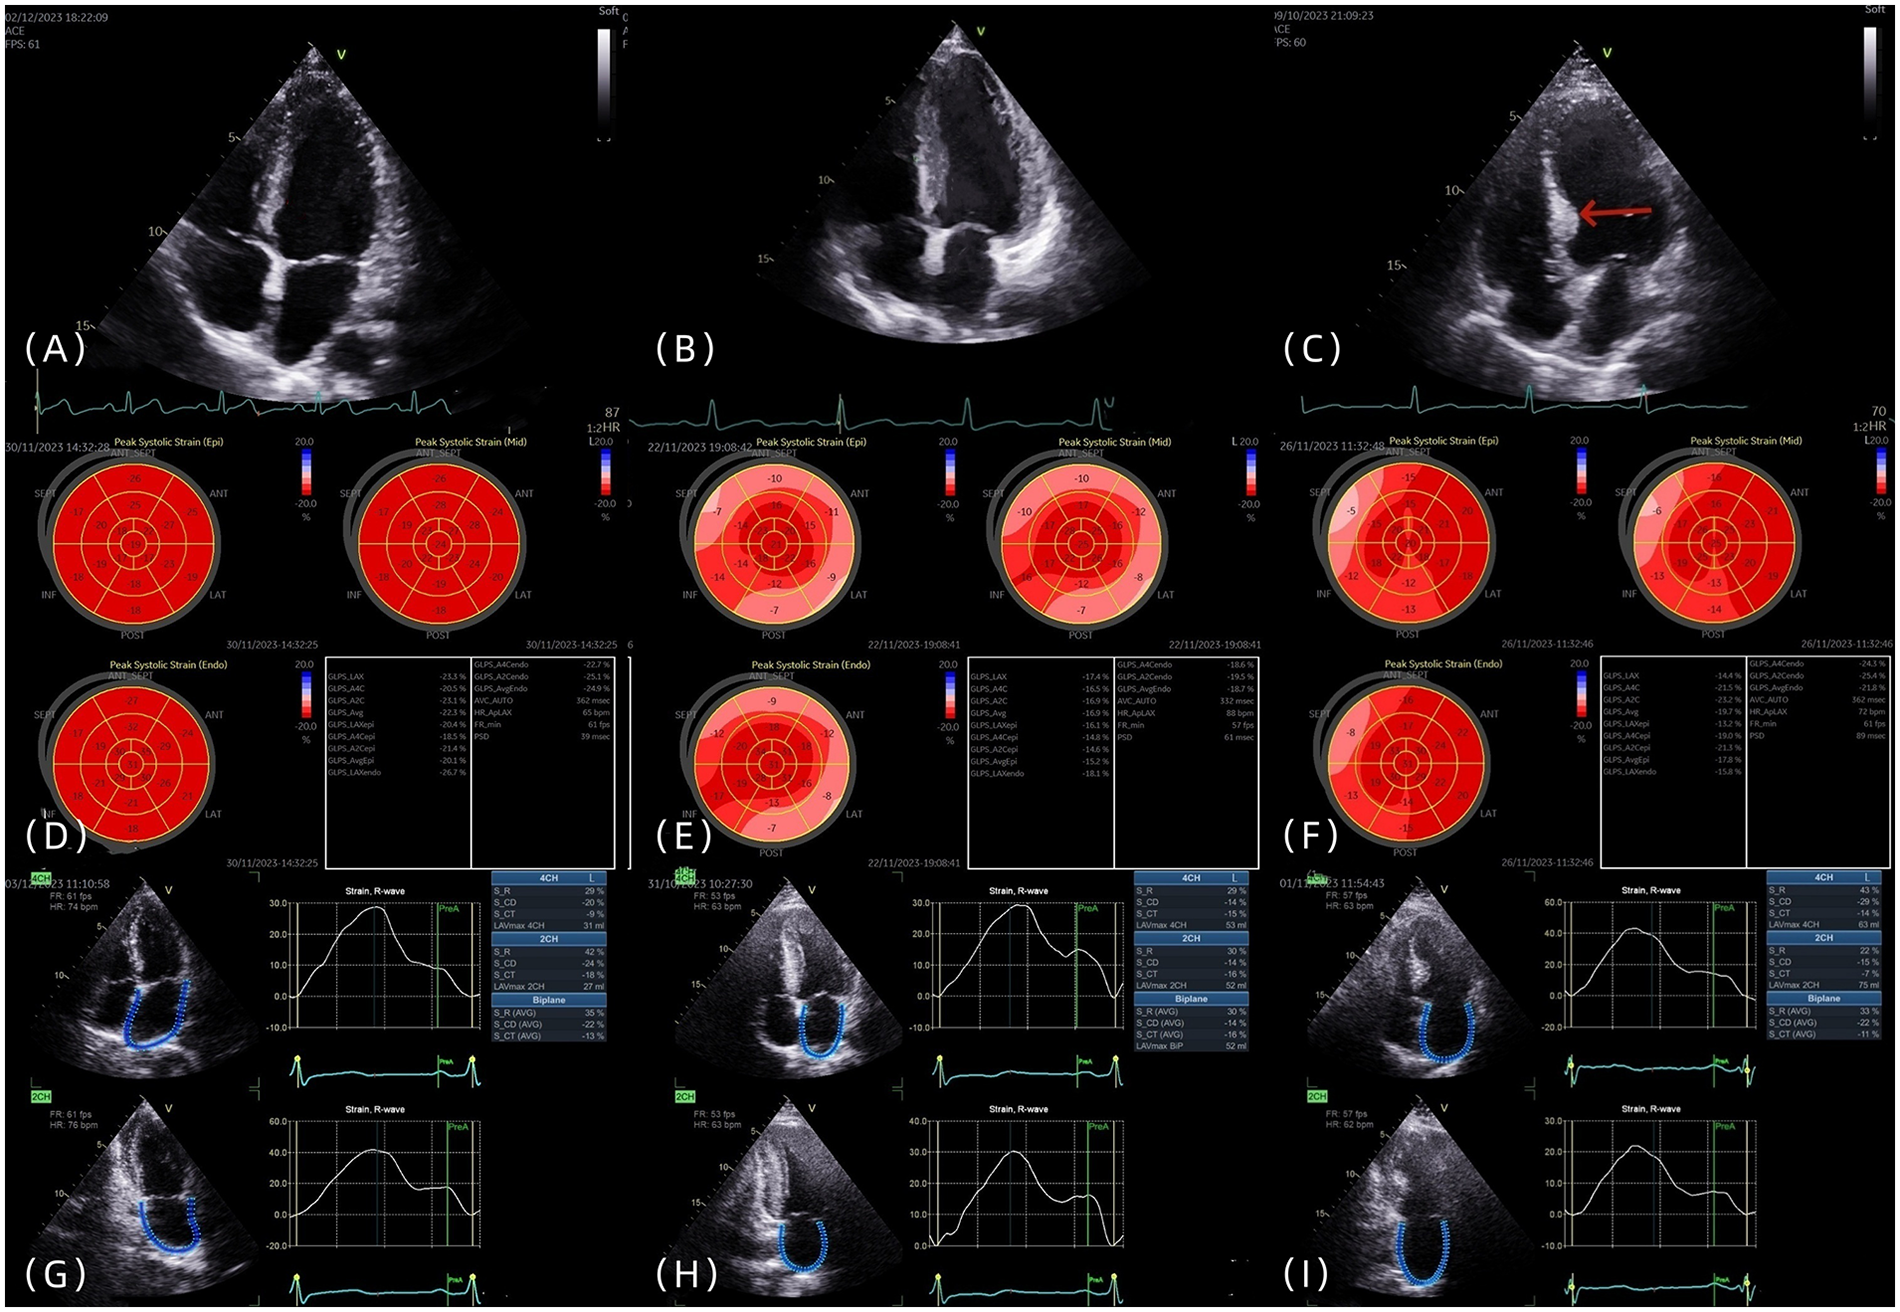

IBSH group: The Framingham inclusion criteria were used as a reference. (1) Localized thickening of the basal septal segment was defined as left ventricular septal basal-segment end-diastolic thickness (LVSBD) ≥ 1.4 cm. (2) The ratio of LVSBD to interventricular septum end-diastolic thickness (IVSD) was required to be ≥1.5. (3) No scarring or segmental wall motion abnormalities were present in the mid-septal segment. (4) Conditions such as aortic stenosis, subaortic membrane, and hypertrophic cardiomyopathy were excluded. All four criteria were required to be met simultaneously (Figures 1A–C).

Figure 1

(A–C) The four-chamber heart views of the control group, LVH group, and IBSH group, respectively, with the arrow pointing to the posterior septal basal segment of the IBSH group. (D–F) The left ventricular strain images of the control group, LVH group, and IBSH group, respectively. (G–I) The left atrial strain images of the control group, LVH group, and IBSH group, respectively.

2.3.3 2D-STI measurement methods

In accordance with the recommendations of the ASE and EACVI, 2D-STI was performed (9). Imaging planes included the apical two-chamber, apical three-chamber, and apical four-chamber views. The average value of all segments was calculated to determine the longitudinal strain at the time of aortic valve closure (AVC), which was used to evaluate LV-GLS (Figures 1D–F). Each wall of the left ventricle was automatically divided into three equal segments (basal, mid, and apical), producing strain values for 18 segments (Figures 1D–F). Subjects with poor image quality, inadequate border tracking, foreshortened views, or missing images were excluded from the analysis.

Left atrial strain was measured using the apical two-chamber and four-chamber views. The zero baseline of the left atrial strain curve was set at left ventricular end-diastole using R–R ECG gating. The endocardial border of the left atrium was manually traced at both left ventricular end-diastole and end-systole, and the average of three consecutive measurements was recorded (Figures 1G–I). Individuals with poor image quality, inadequate border tracking, foreshortened views, or missing images were excluded from the analysis.